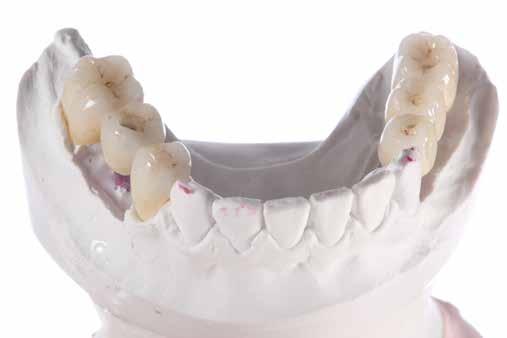

Teljes ívű rehabilitáció primer vázra ragasztott lítium-diszilikát szekunder koronákkal

A tesztprojektünk megerősítette, hogy a KATANA Zirconia

potenciállal rendelkezik, és az indikációs területe határtalan.

pozicionálása a virtuális nyersdarabban, marás után pedig az illeszkedés

Zirconia YML kiváló minőségű anyag, amely nagy esztétikai határtalan. Meglepően egyszerű a restaurációk tervezése és pedig a felületek simák, a szélek élesek és határozottak, pedig pontos.

Amikor a fogászati cirkónium rendkívül esztétikus anyaggá fejlődött alkalmassá válva a monolitikus kialakítású vagy minimális labiális visszavágású pótlások készítésére, a kézzel végzett munka (kerámia rétegezés) mennyisége csökkent. Ugyanakkor minden fogtechnikai laboratóriumnak több elérhető nyersdarabra volt szüksége, és az indikáció-specifikus anyag -

választás igénye bonyolította a tervezési folyamatokat.

Egyes fogtechnikusok előszeretettel játszanak a különböző korongokkal és az automatizált és kézi munkafolyamatok kombinációjával, hogy pontosan megfeleljenek a páciens és az indikáció-specifikus igényeknek. Mások azonban egy gyorsabb és szabványosabb utat választanának